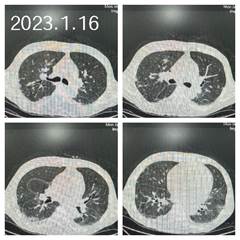

患者胸部CT影像学表现

1月3日,一名糖尿病肾功能衰竭合并新冠病毒重症感染的患者由商洛地区转诊至我院重症肾脏病•血液净化科。该患者既往有糖尿病史20年,高血压病史4年,冠心病史4年,2年前开始规律血液透析。入院时患者呼吸困难,静息状态下指脉氧饱和度只有75%。急查的生化指标显示肌红蛋白10981ng/mL、高敏肌钙蛋白I大于50000pg/mL、降钙素原30.6ng/mL、白介素-6 357pg/mL、C反应蛋白231mg/L、淋巴细胞计数0.09*109/L、血钾5.77mmol/L。患者低氧血症严重,无法正常前往CT室进行胸部CT检查,但是又急于了解患者肺部感染情况,蒋红利主任积极联系CT室牛刚主任,开通紧急检查绿色通道,在高菊林护长、刘小敏护长及严森辉医生的严密组织下,大家推着氧气瓶,带着抢救药品,为患者进行了急诊胸部CT检查。

在整个救治过程中,在蒋红利主任的带领下,以史珂慧副主任医师、王萌主治医师、严森辉住院医师和杨蓉蓉进修医师为主的医疗小组,及以高菊林护士长、刘小敏副护士长、薛小红主管护师、李宁主管护师为主的护理小组齐心协力救治患者。相关科室医生如重症医学科李昊副主任和高兰主治医师以及消化科马富权主治医师等在诊疗中也给出了宝贵的诊疗建议。功夫不负有心人,在科室医护的精心治疗和护理下,入院第三天,患者的体温逐渐恢复正常,肺部渗出性病变也逐渐吸收,入院第十天,改为鼻导管吸氧,指脉氧饱和度为100%,入院第15天逐渐过渡到普通血液透析,1月18日这位危重症患者康复并顺利出院。出院前患者及家属给病房赠送锦旗,感谢医务人员的精心治疗和辛勤付出。